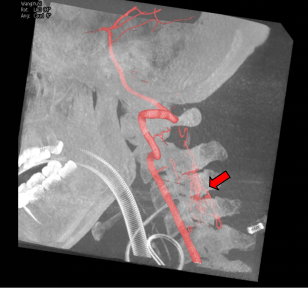

畸形血管团切除后立即脊髓造影明确完整切除

切除完成后,再次进行了造影复核,确认畸形血管团已被完全切除,手术取得了圆满成功。

凭借丰富的经验,结合造影结果及解剖定位,精准在病灶背侧沿后正中沟切开脊髓,终于发现了深藏于髓内的畸形血管团,清除了髓内血肿,并完整切除了该畸形血管团。整个手术过程都在神经电生理监测下进行,确保手术操作不会对正常神经组织造成额外损伤。